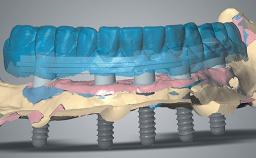

Rehabilitating an Edentulous Maxilla with a Fixed Dental Prosthesis Using a DSD-Guided Approach

A 60-year-old man was referred to the Center of Excellence for Prosthodontics and Implant Dentistry (CEPI) of the School of Dentistry of the University of São Paulo, Brazil for implant therapy. Anamnesis, clinical examination, and radiographs revealed esthetic and functional problems, the absence or structural compromise of various teeth (16–11, 21, 22, 24, 25, 37, 45, and 48), periodontal and endodontic problems (17 and 27), implant fracture (46), and occlusal disorders . The patient reported that he was undergoing treatment for cardiovascular diseases.